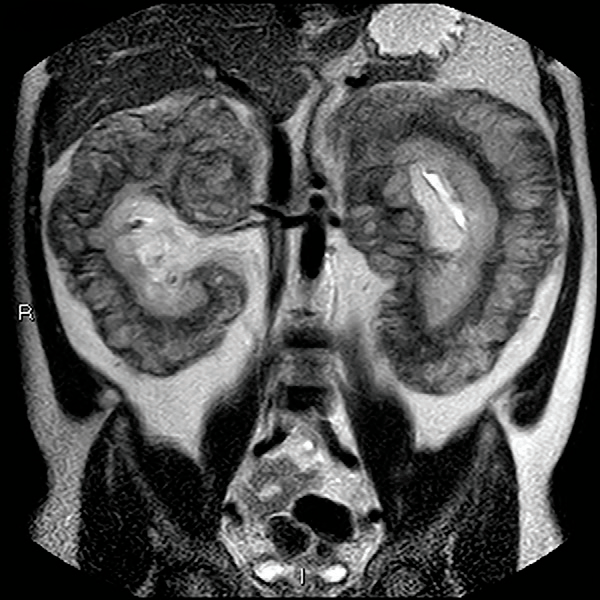

Figure 1:

MRI T2加权冠状位图像显现双侧肾周有大量软组织肿块浸润,可见“毛肾征”。

Erdheim-ChesterECD是一种稀有的多系统非朗格汉斯组织细胞增加症,近年来被以为是一种克隆性疾病。好发于长骨和腹膜后,肾周脂肪浸润构成典型的针状外观(即 “毛肾征”)。由于本例患者 病程长,临床病症不明显,招致肾周组织大量浸润,使经典的 “毛肾征”影像学征象变成了不典型的肿块状粗笨外观。